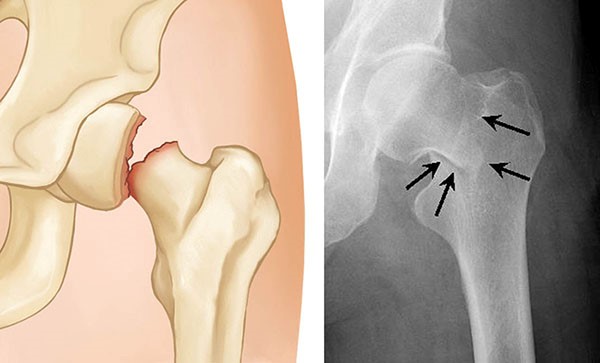

Uma fratura de quadril pode ocorrer em uma das quatro áreas do fêmur superior:

- Colo femoral: área do fêmur abaixo da cabeça femoral;

- Área transtrocantérica: área abaixo do colo do fêmur e acima da parte longa ou diáfise do fêmur. É chamado de transtrocantérica, ou intertrocantérica, porque é marcado por dois marcos ósseos: o trocânter maior e o trocânter menor;

- Área subtrocantérica: parte superior da diáfise do fêmur, abaixo dos trocânteres maior e menor;

- Cabeça femoral: área arredondada da extremidade do fêmur.

As fraturas transtrocantéricas e do colo do fêmur são os tipos mais comuns de fratura de quadril. As fraturas da cabeça do fêmur são extremamente raras e geralmente são resultado de um acidente de alta velocidade.

As áreas do fêmur (osso da coxa). A maioria das fraturas de quadril ocorre no colo do fêmur ou na área intertrocantérica.